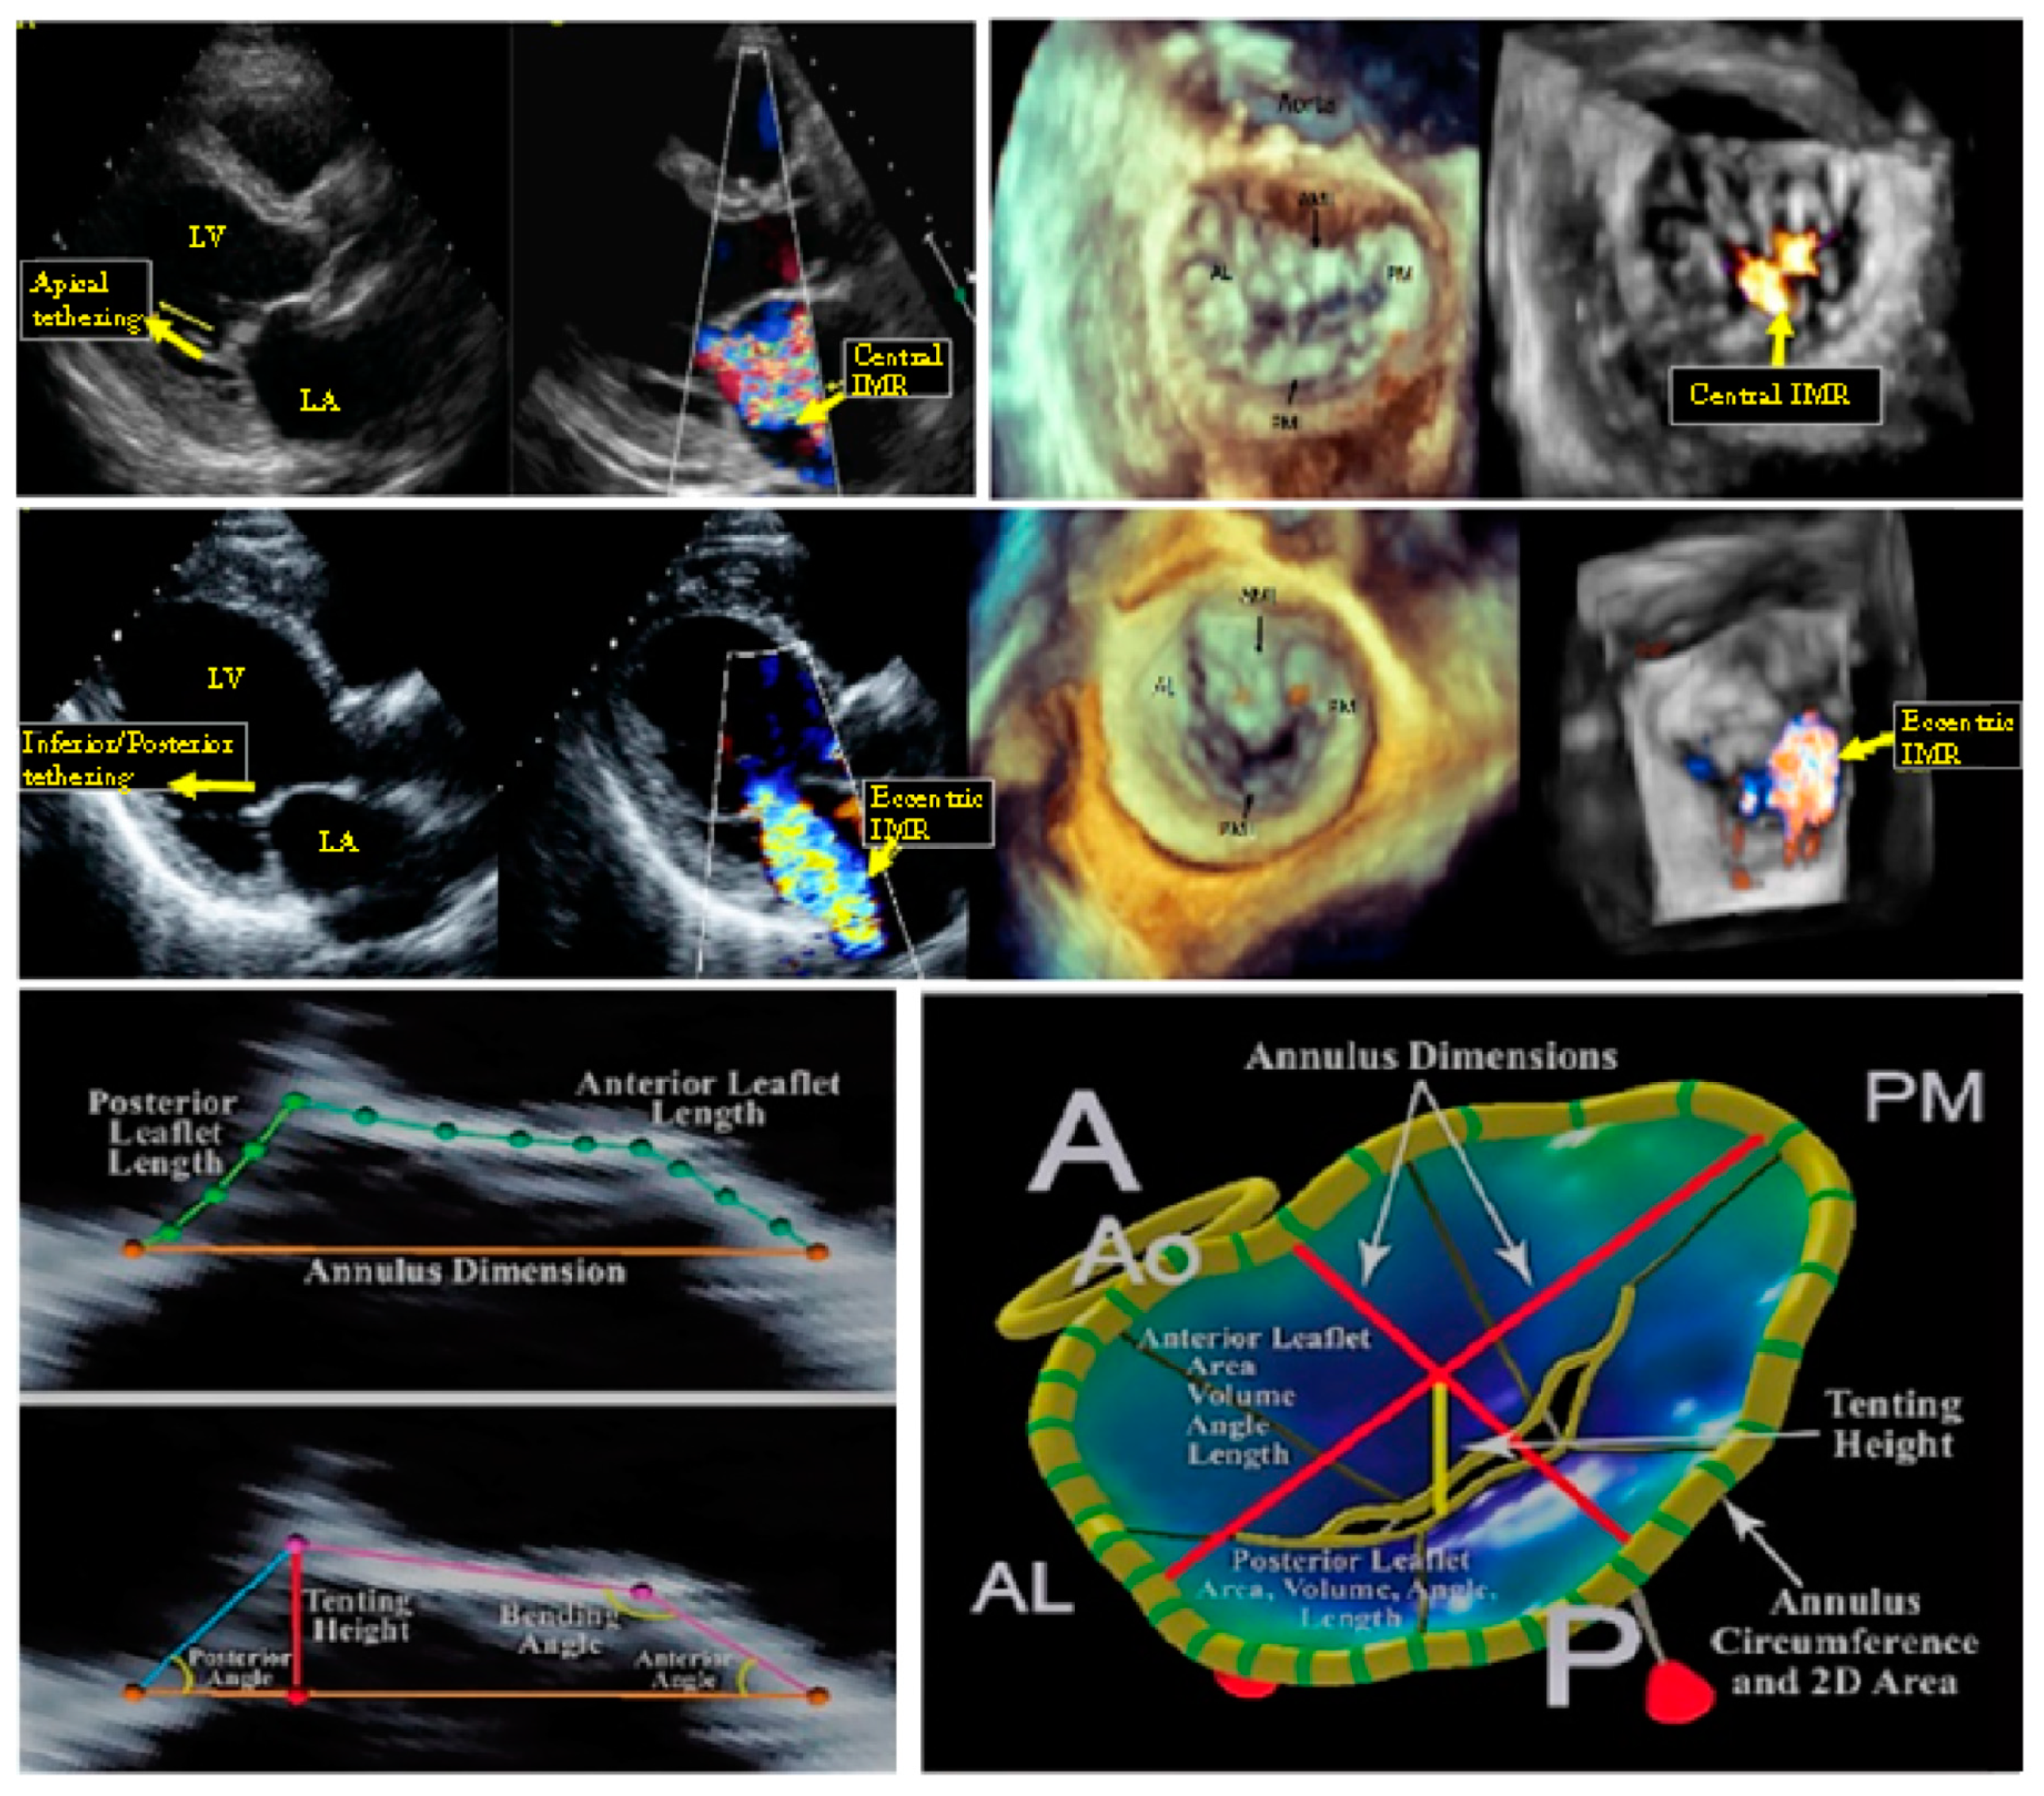

3.1. Mitral Valve: Annulus and Leaflet

3.2. Mitral Valve: Subvalvular Apparatus

3.3. Combined Valvular and Subvalvular Model